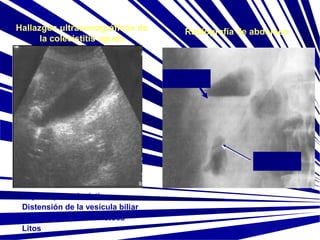

Hallazgos ultrasonográficos de

la colecistitis aguda

Radiografía de abdomen

Distensión de la vesícula biliar

Pared vesicular edematosa

Litos